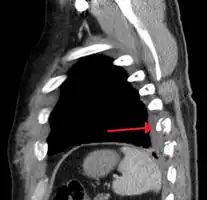

Two broken ribs as seen on parasagittal CT